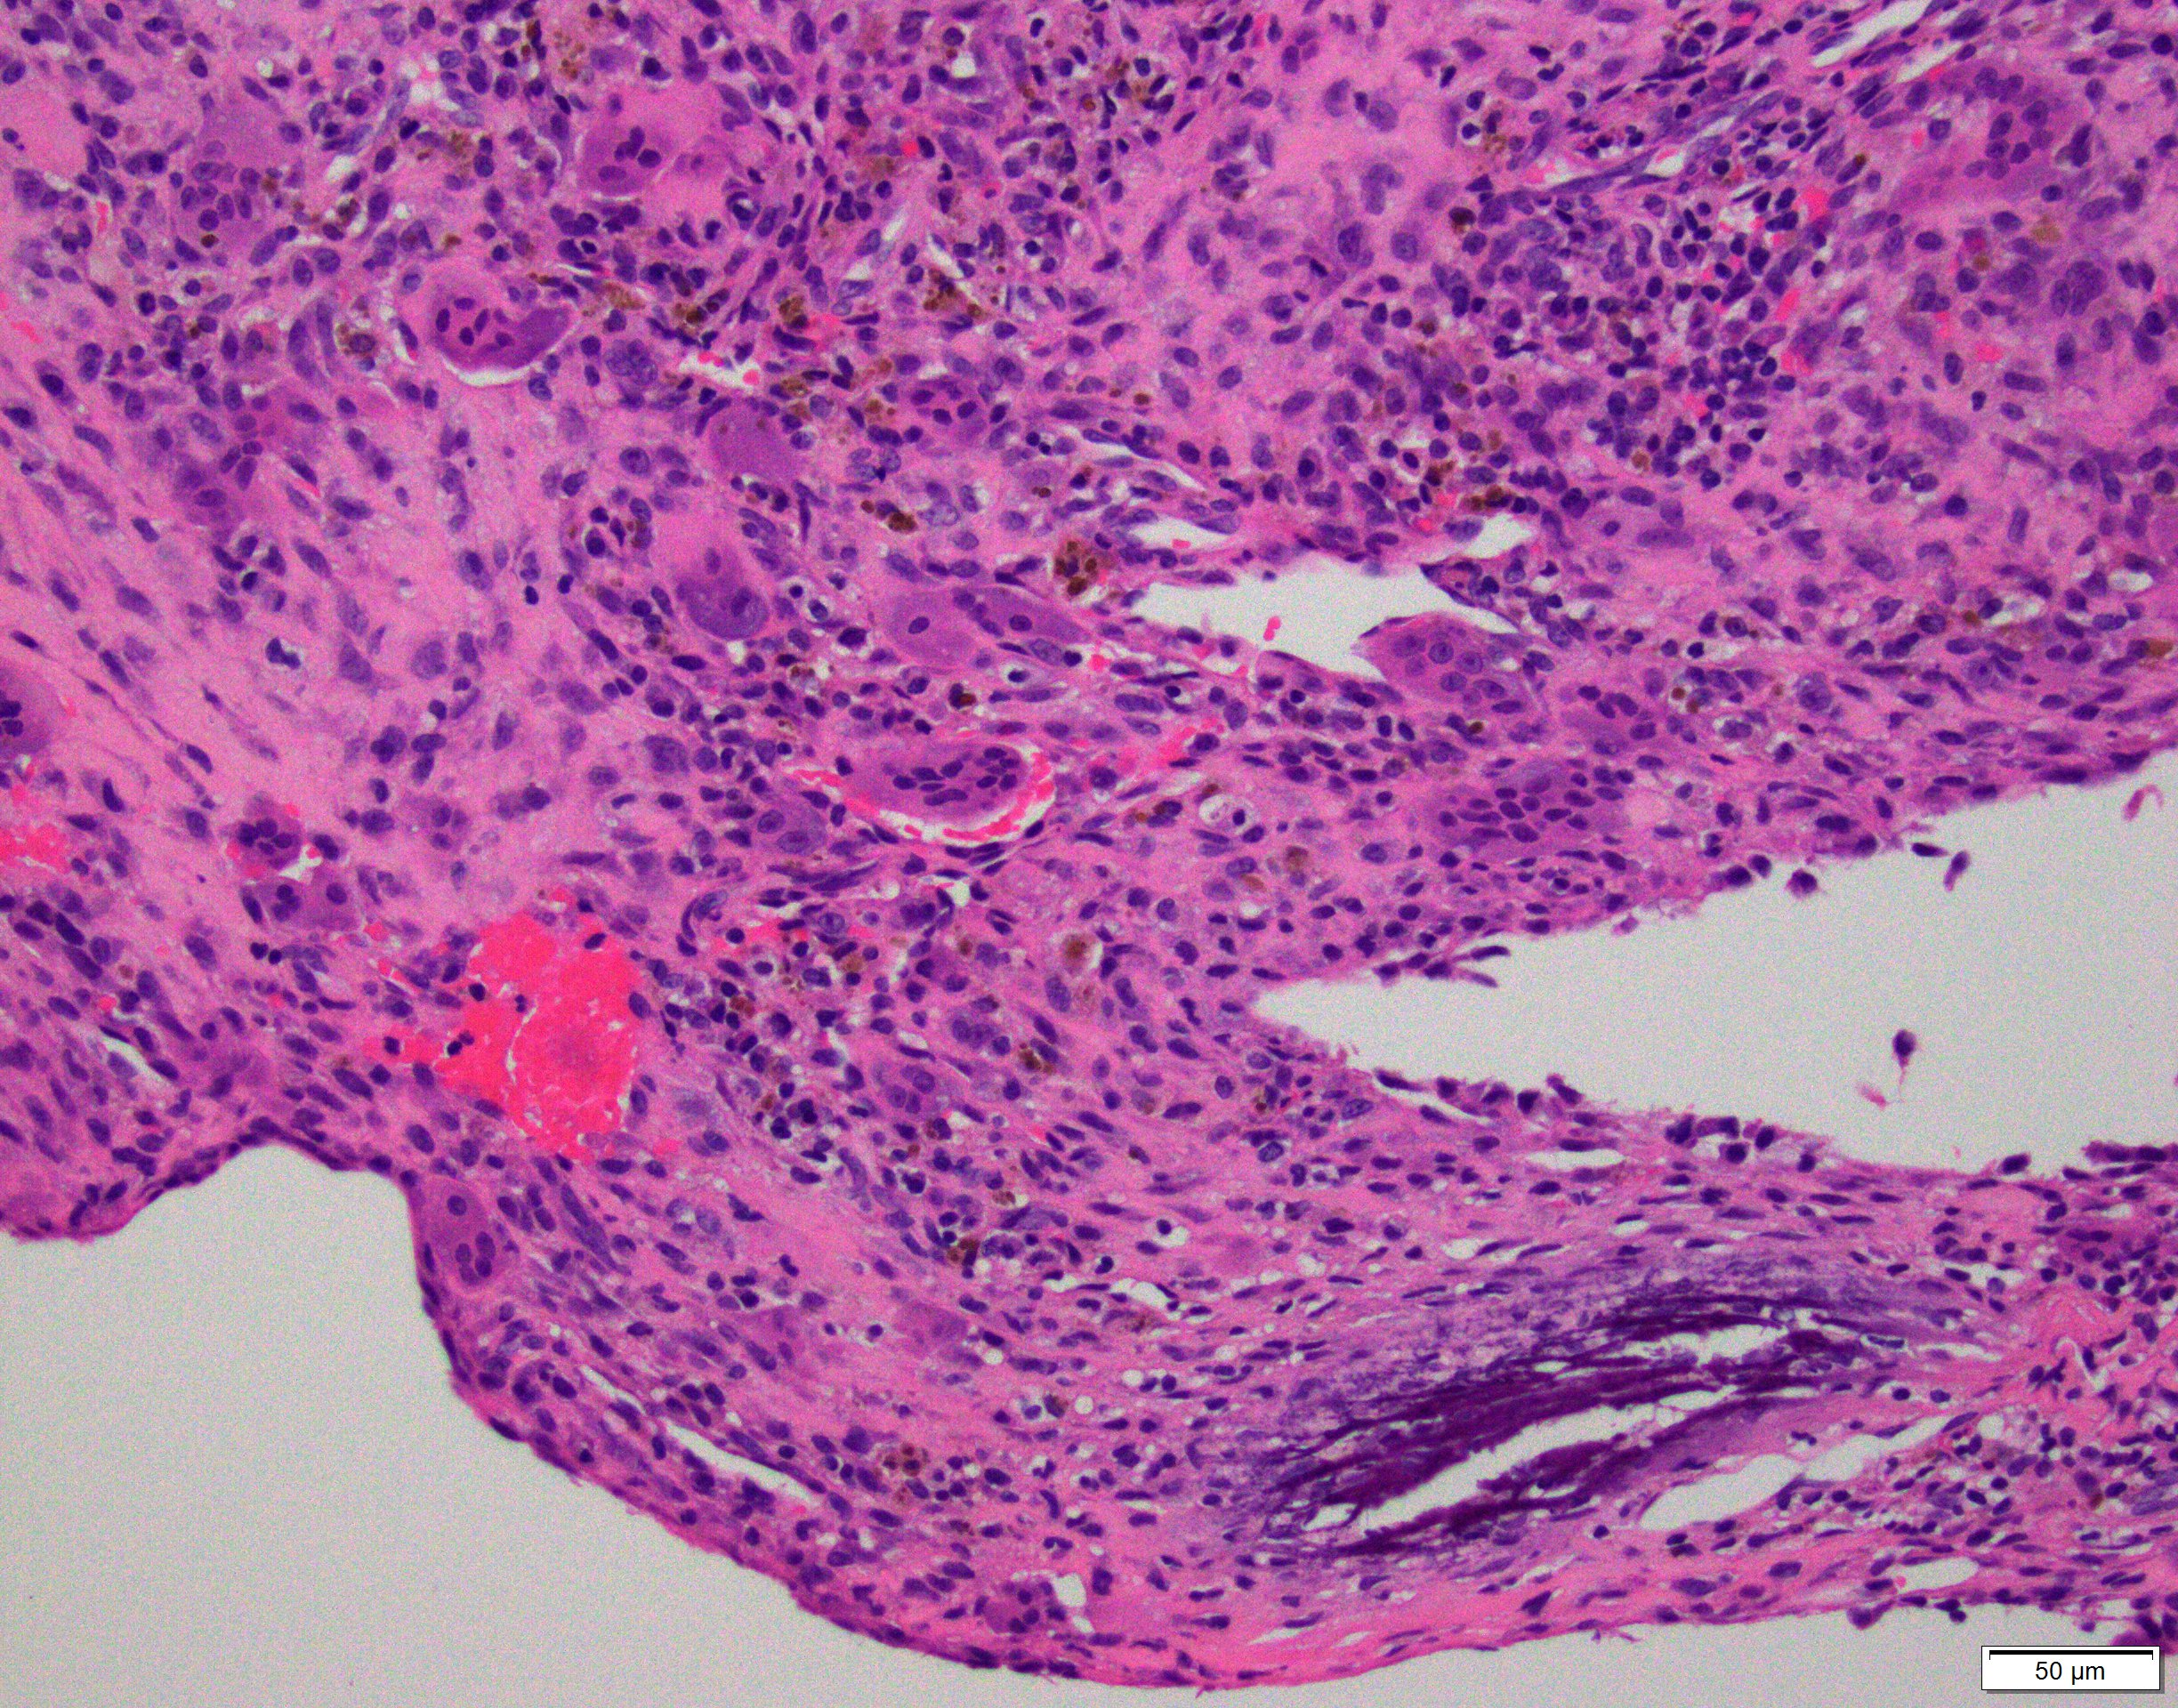

- Multiloculated cystic lesion

- Blood filled cystic spaces separated by cellular septa containing fibroblasts, giant cells and woven bone

- Calcified, basophilic material (blue reticulated chondroid-like material)

- Necrosis not common but mitotic activity is easily identified

- No cytologic atypia (Am J Clin Pathol 2015;143:823)

- Numerous giant cells in connective tissue that line large sinusoidal spaces

Microscopic (histologic) images

Contributed by Elham Nasri, M.D. and Kelly Magliocca, D.D.S., M.P.H.

A. Aneurysmal bone cyst. The H&E shows cystic spaces with stromal giant cells. Rearrangement of USP6 gene confirms the diagnosis in the above clinical and radiographic context.